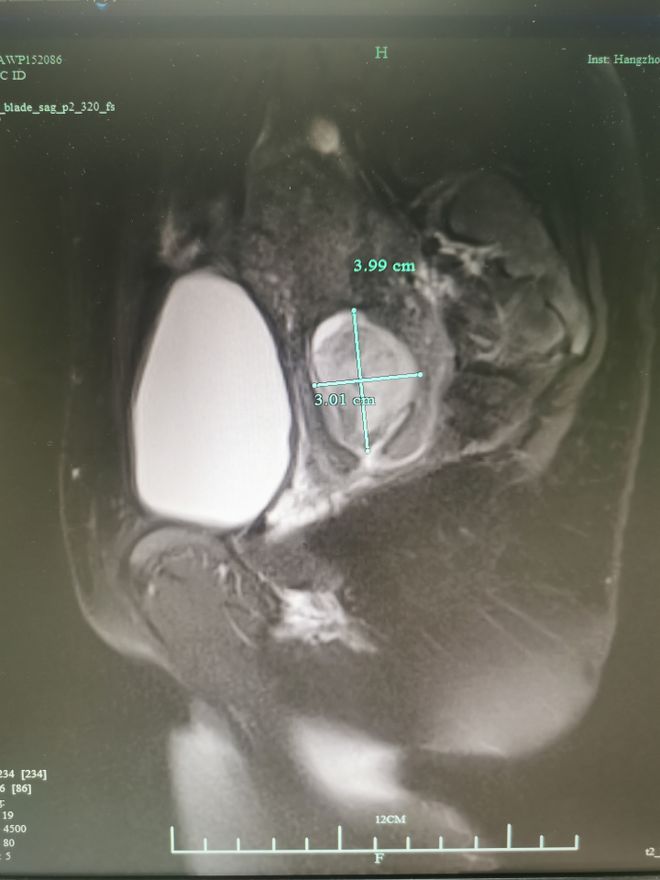

检查发现,杨女士的宫颈上长了 一个直径大约4公分的肿块, 这次阴道出血并不是月经,而是这个肿块导致的。

△杨女士MRI提示宫颈异常回声,可见4cm的巨大囊性病灶

杨女士告诉赵医生,6月她在其他医院做了B超,提示宫颈上有个2公分左右的小囊肿,身体也没出现什么特别的症状,就没多在意,没想到它竟然短时间变大这么多,还造成了出血。

这个“肿块”几乎同一个鸡蛋大小,长得还不慢,是良是恶?